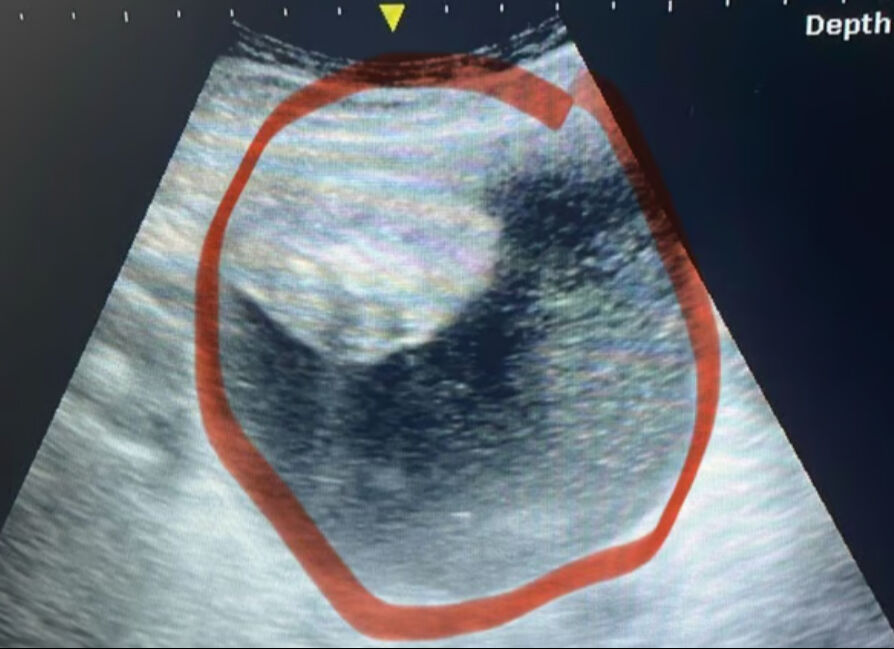

Yapılan birçok test sonucu hamile olmadığı tespit edilen kadın, ultrasona girdi. Doktorların hastalığı tespit edemediğini bildiren genç kadın, "Görebildikleri tek şey mesaneme baskı yapan büyük, sıvı dolu bir kitleydi'' dedi ve ekledi:

''Bunun bir kist, fıtık mı yoksa tamamen başka bir şey mi olduğundan emin değillerdi."

Kitlenin çok hızlı büyüdüğü vurgulanırken, Gerrits, ''Cuma günü 12 santimetre olan kitle, Pazartesi 17 santimetreye ulaşmıştı. Çok hızlı büyüyordu'' dedi. Acil ameliyata alınan kadının yumurtalığı kurtarıldı.Biyopsi sonucu, tümörün kötü huylu ve ileri seviyede olduğunu ortaya çıkardı.